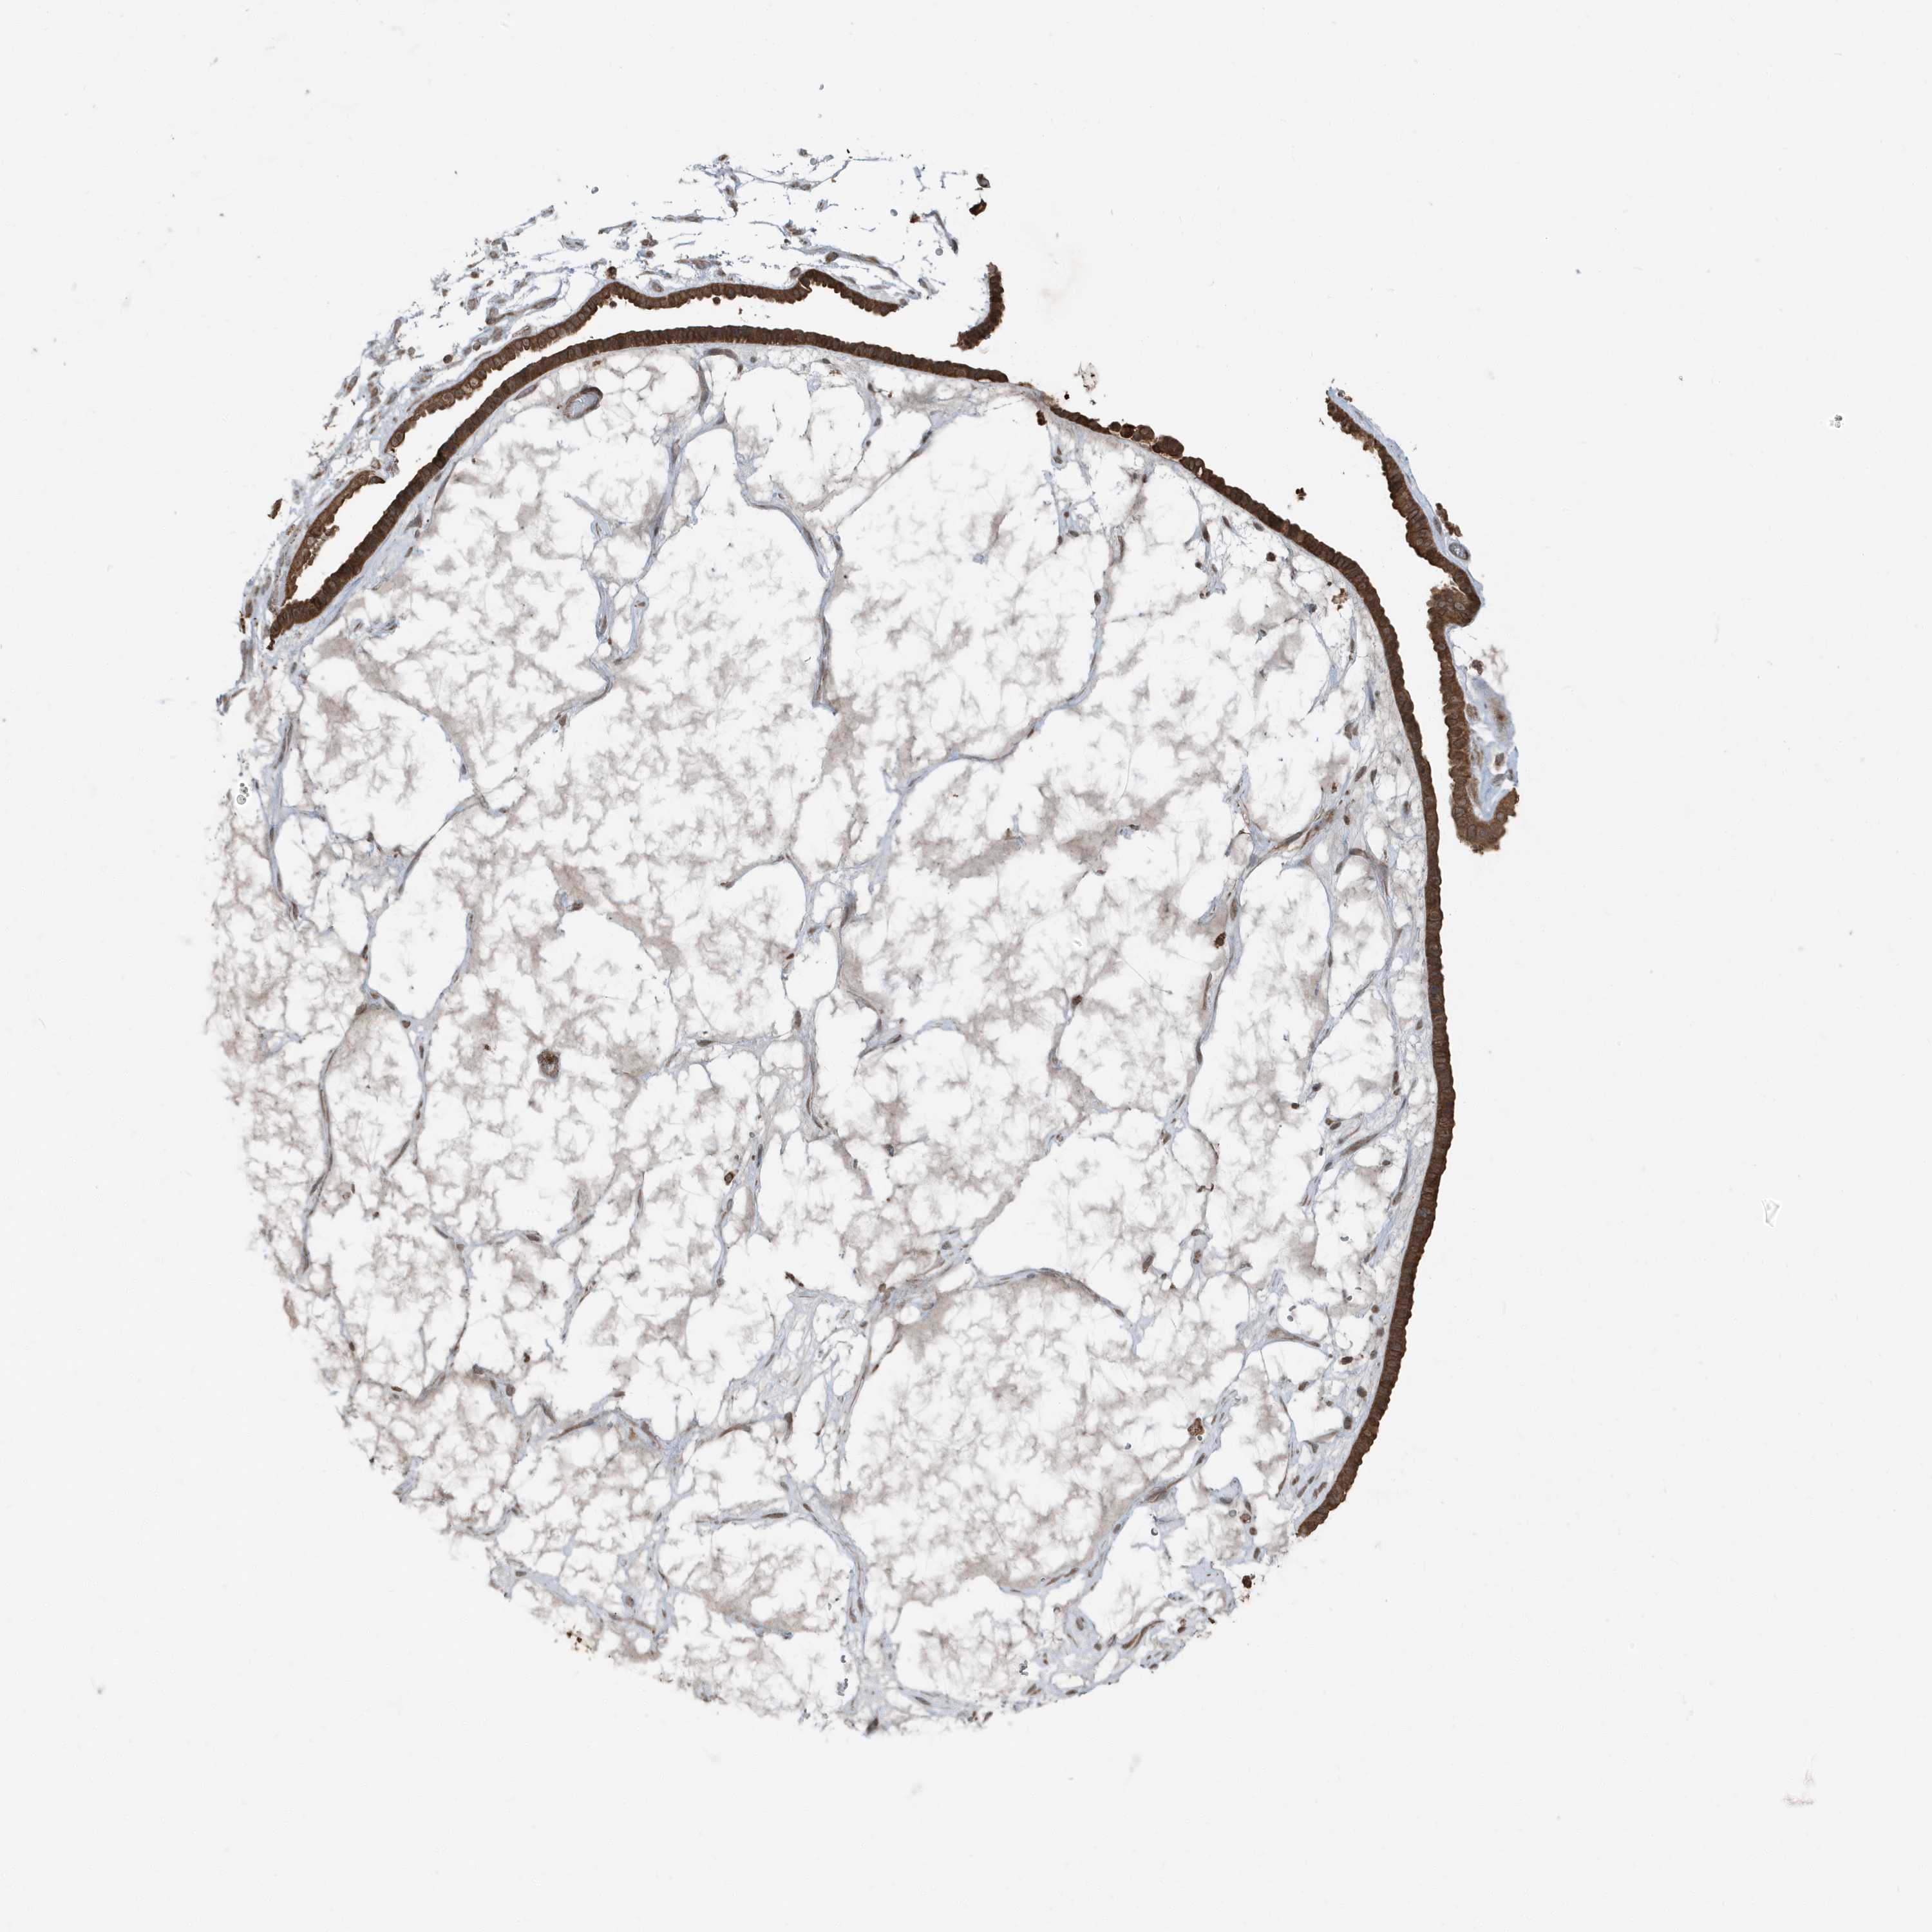

OVARIAN CANCER - Protein expressioni

A mouse-over function shows sample information and annotation data. Click on an image to view it in a full screen mode. Samples can be filtered based on level of antibody staining by selecting one or several of the following categories: high, medium, low and not detected. The assay and annotation is described here.

Note that samples used for immunohistochemistry by the Human Protein Atlas do not correspond to samples in the TCGA dataset.

Antibody stainingi

Antibody staining in the annotated cell types in the current human tissue is reported as not detected, low, medium, or high, based on conventional immunohistochemistry profiling in selected tissues. This score is based on the combination of the staining intensity and fraction of stained cells.

Each image is clickable and will lead to virtual microscopy that enables deeper exploration of all samples and also displays staining intensity scores, fraction scores and subcellular localization as well as patient and tissue information for each sample.

Antibody HPA035258

Cystadenocarcinoma, serous, NOS

Carcinoma, endometroid

Cystadenocarcinoma, mucinous, NOS

Carcinoma, NOS